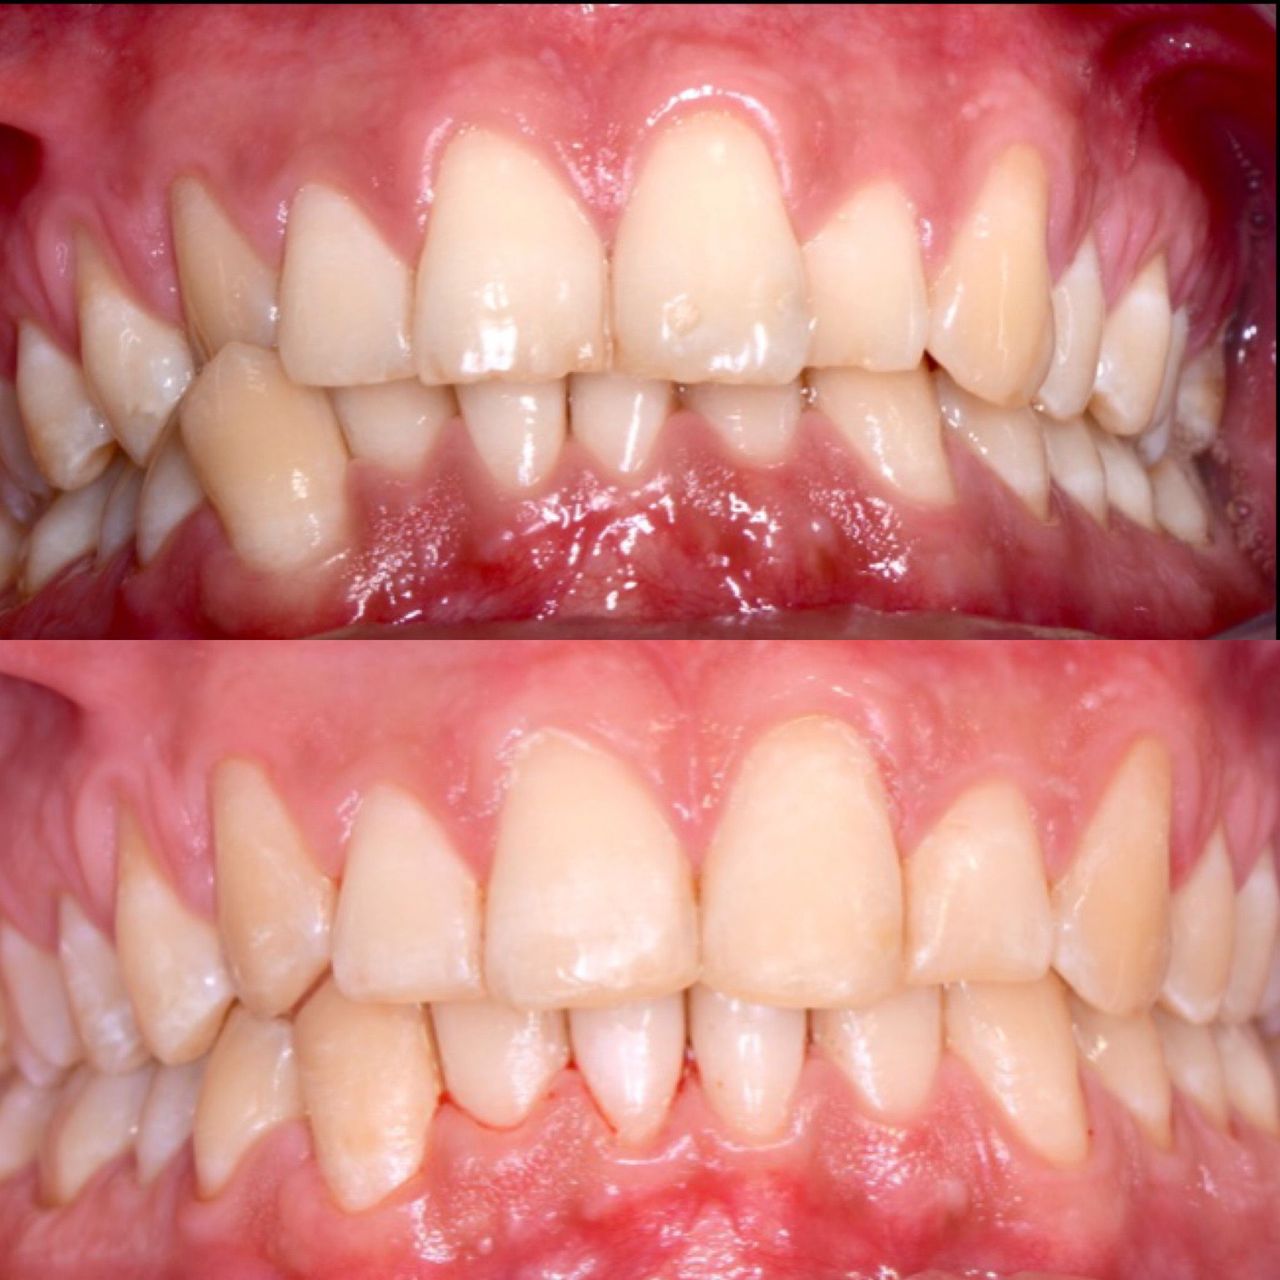

Foto e video